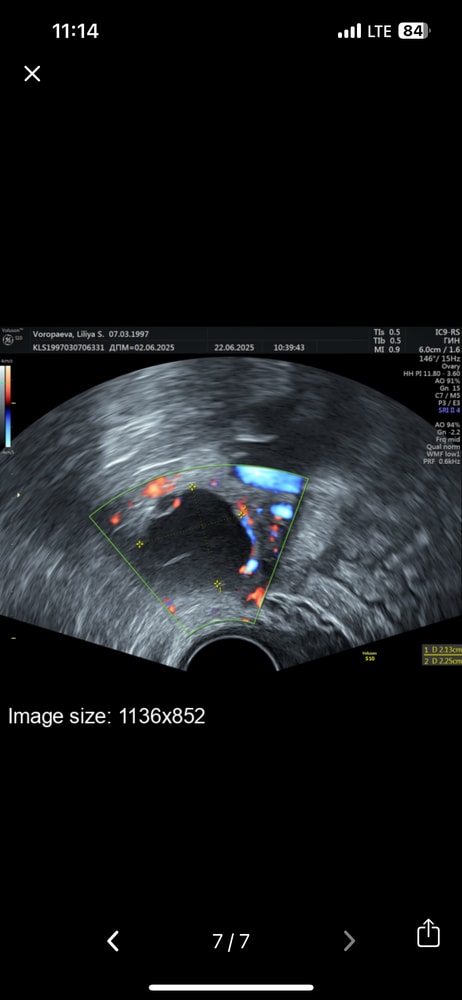

Лиличка в Зачатие 6 месяцев Желтое тело УЗИ Добрый деньБыло ли у кого желтое тело с тонкой перегородкой?Либо могло просто на него что то наложиться?Есть ли вероятность беременности с таким жт Посмотрите еще 20 записей на эту тему Отменить Ответить Овуляция. Симптом «зрачка» отрицательно Нашли мою маленькую бусинку Чаты Беременных Выберите чат: Январята-2026 Февралята-2026 Мартята-2026 Апрелята-2026 Майчата-2026 Июнята-2026 Июлята-2026 Августята-2026